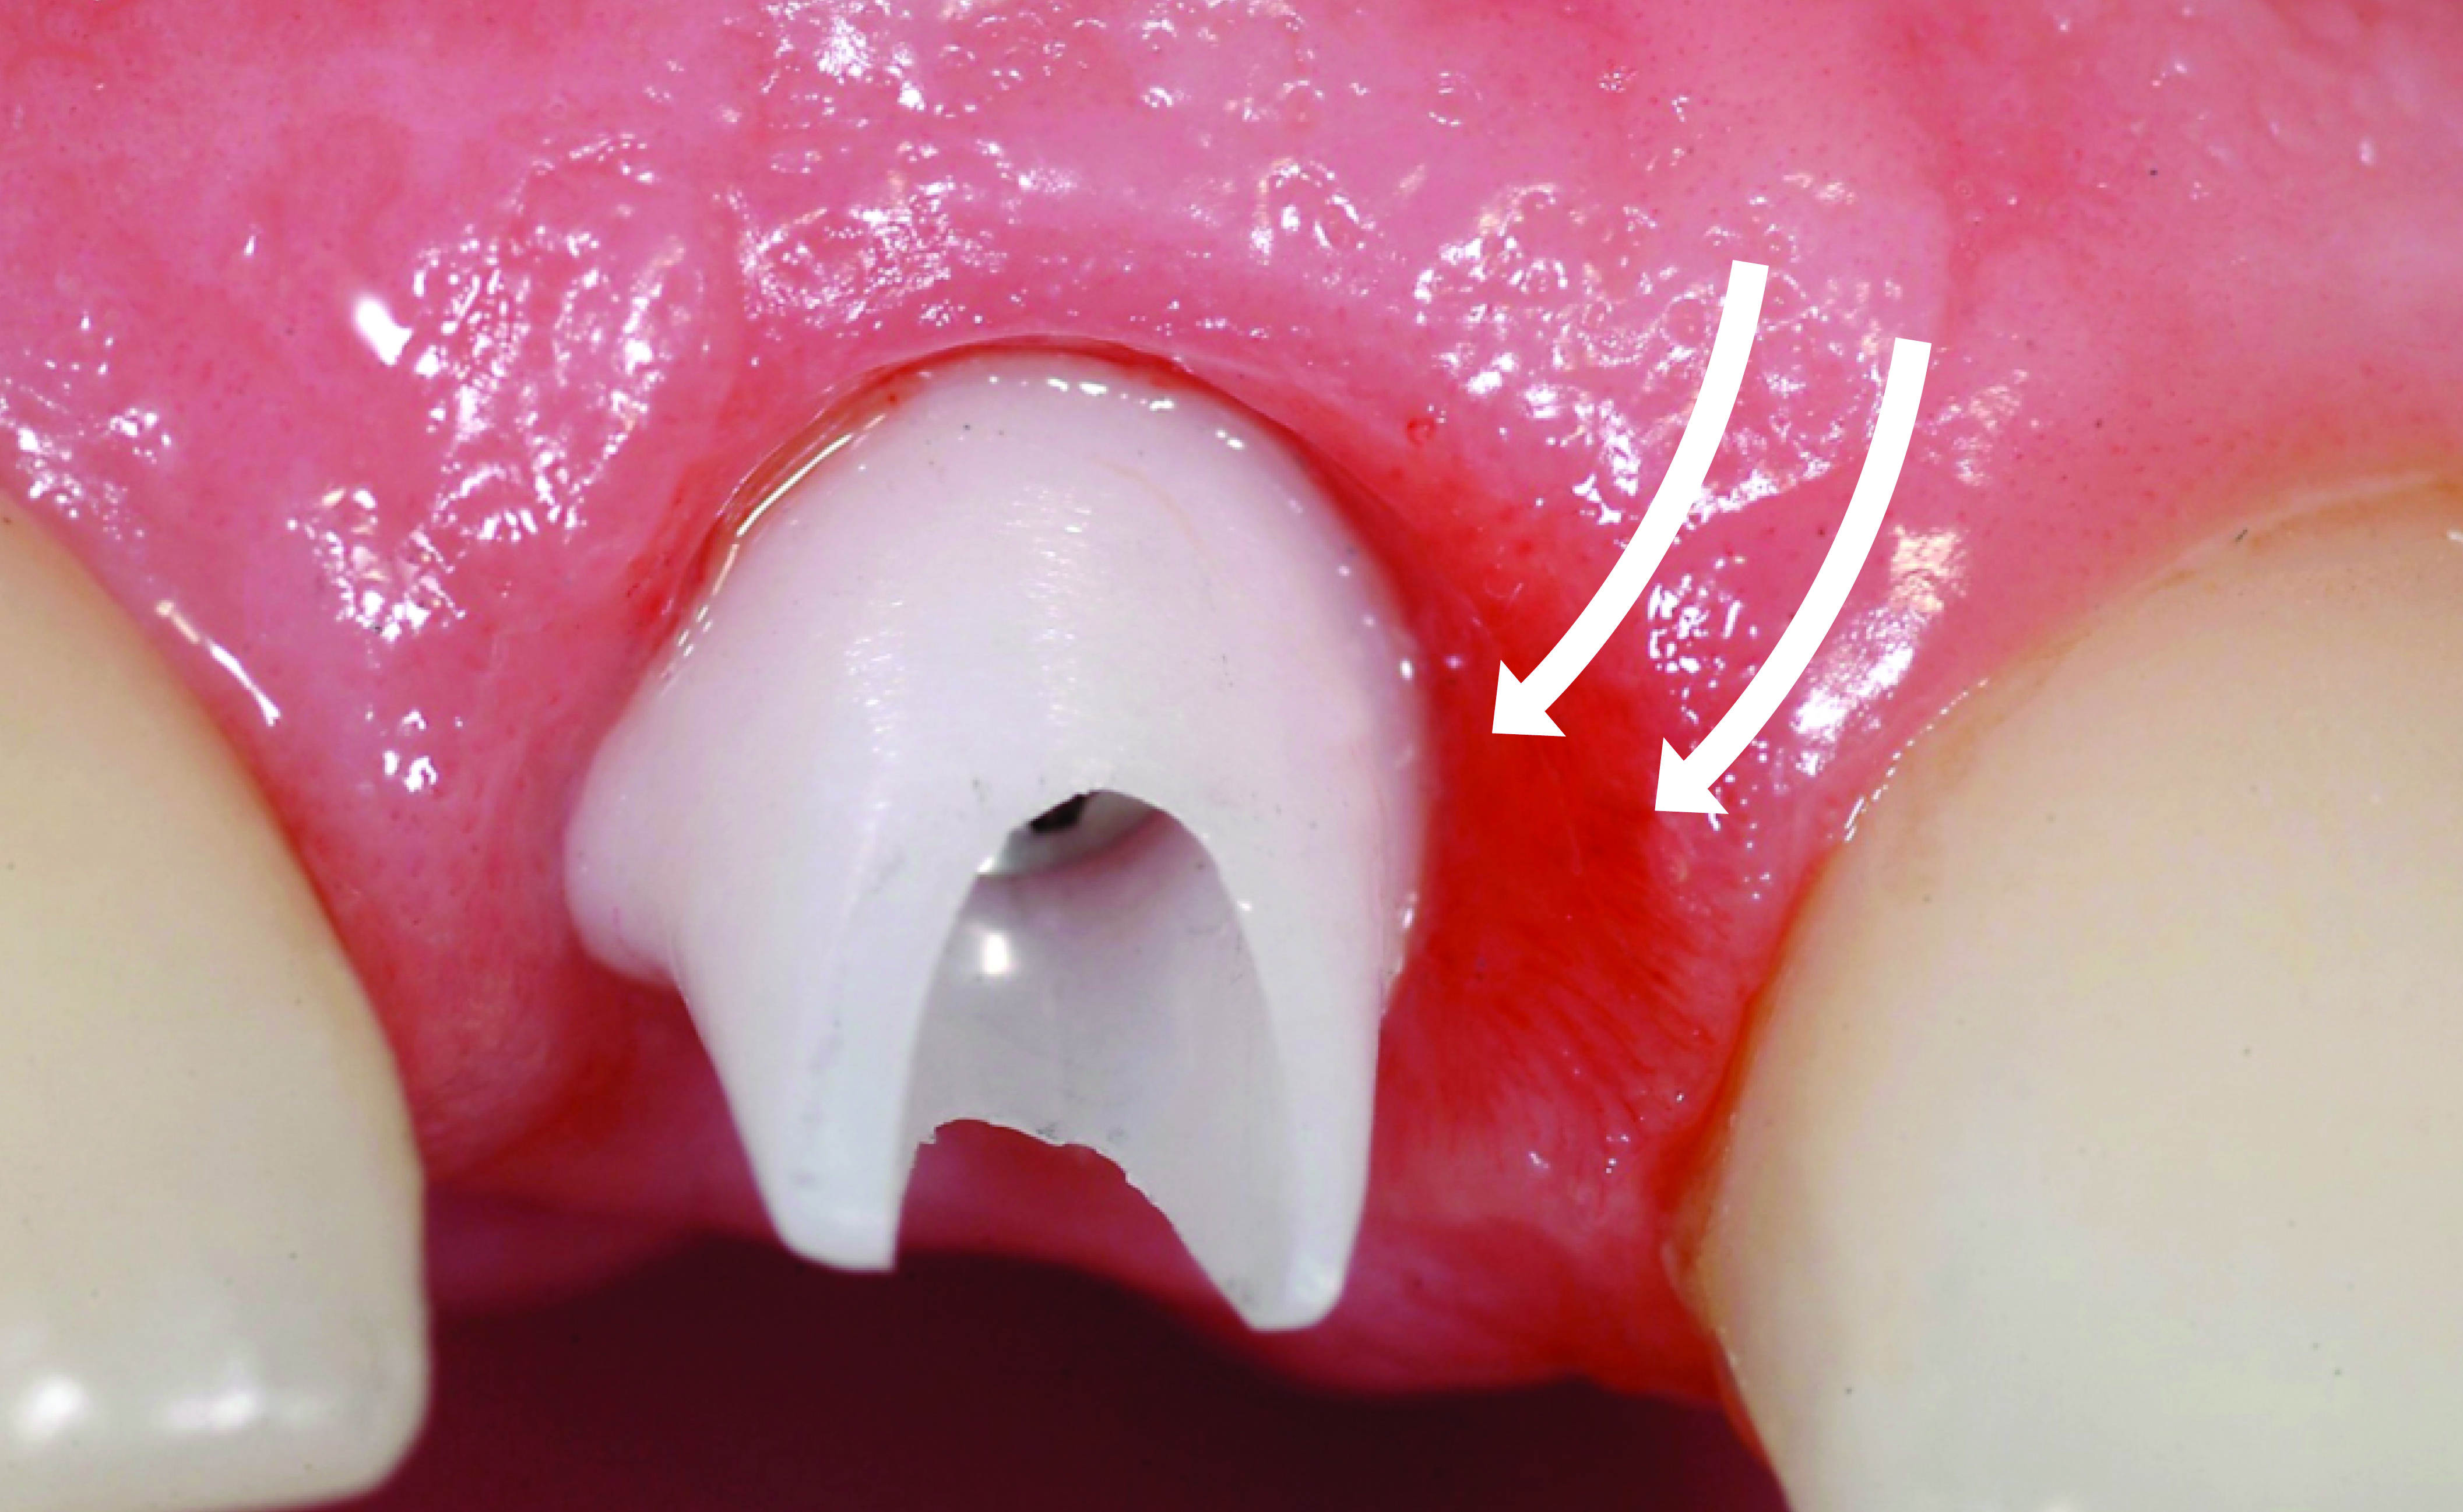

Fig 18. After immediate implant placement and provisionalization, the removal of the temporary crown reveals a healthy and shaped gingival sulcus of favorable volume.

Figure 18